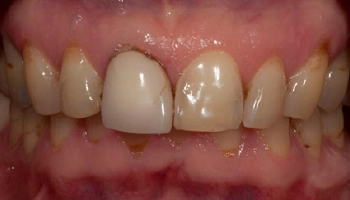

Trauma: Implant, crown & veneer

Before and after dental restoration with implant, crown, and veneer. After dental restoration featuring an implant, crown, and veneer.